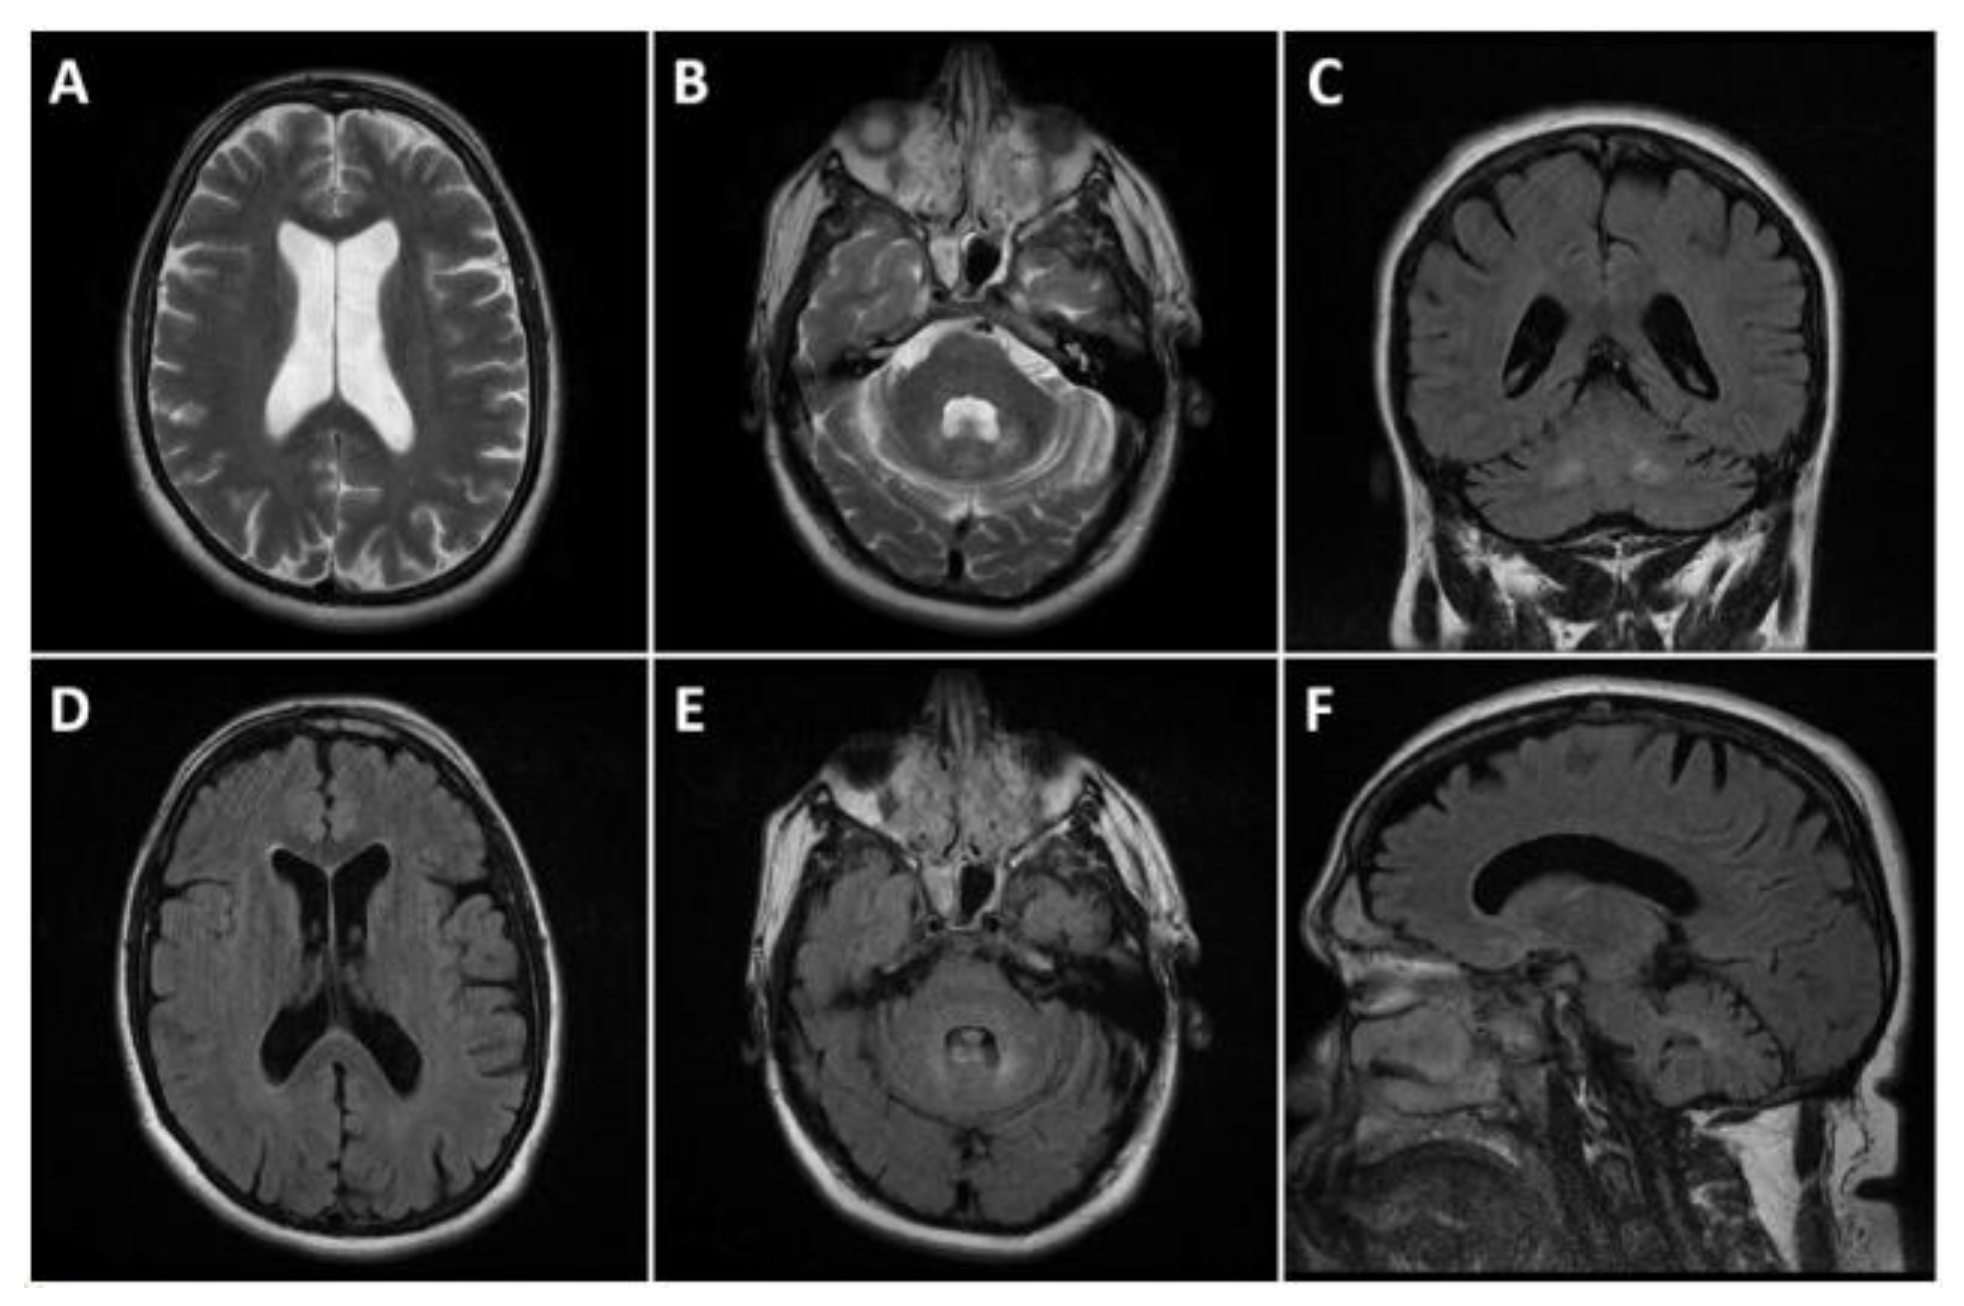

2. Case Presentation